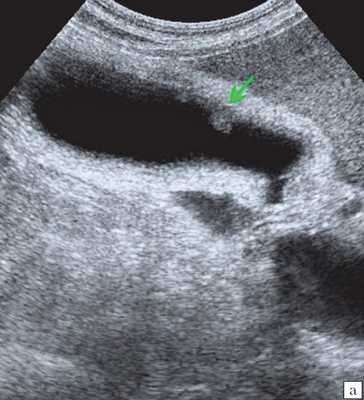

- Ультразвуковая диагностика. К визуализирующим методам диагностики холангита относятся УЗИ брюшной полости и печени, ультрасонография желчных путей. С их помощью удается получить изображение желчных протоков, выявить их расширение, определить наличие структурных и очаговых изменений в печени.

Ультрасонография является эффективным средством выявления полиповидной формы холестероза 8. Традиционной считается следующая сонографическая характеристика холестериновых полипов: неподвижные гиперэхогенные структуры, которые не дают акустической тени и прикрепляются к стенке желчного пузыря. Контуры таких образований, как правило, ровные, а размеры таких образований различны, чаще не превышают 10 мм (рис. 2).

a) Одиночный полип в желчном пузыре (гиперэхогенное пристеночное неподвижное образование, с ровными контурами, без акустической тени).

б) Одиночный полип в желчном пузыре.

в) Полиповидно-сетчатая форма холестероза, полипы размерами до 5 мм, повышенной эхогенности.

г) Одиночный полип в желчном пузыре.